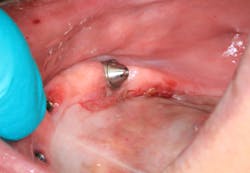

Clinical assessment revealed a white, corrugated lesion lingual to the acrylic of the fixed hybrid prosthesis (figure 2). The lesion measured 5x24 mm and was not able to be scraped off or removed. It was not painful or symptomatic, and no swellings were noted in the sublingual or submandibular lymph node areas (figures 3 and 4).

The unknown etiology of the lesion automatically put it into a category of high-risk leukoplakia, especially since it had just recently manifested and there had been a history of previous biopsy to the area that was diagnosed as precancerous tissue. The patient was seen in my office for prosthesis removal and then referred to an oral surgeon, where she had an excisional biopsy under local anesthesia (figures 5 and 6). The patient's prosthesis was adjusted and appropriate follow-up care was put in place.